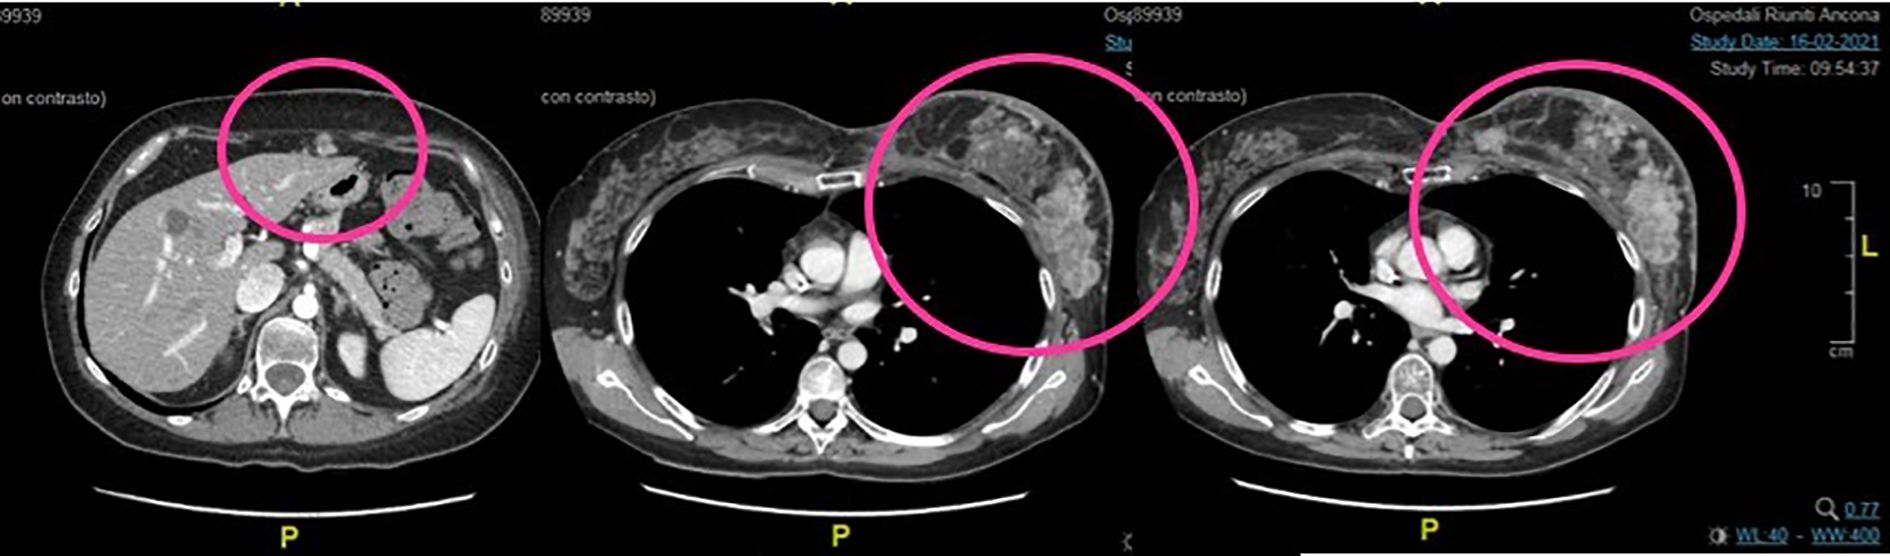

In February 2021, a total body CT scan confirmed the high clinical suspicion of progressive disease with peritoneal carcinosis, multiple subcutaneous lesions in the chest wall (Figure 2), multiple nodes, and lung metastasis. Taking into account the absence of available standard therapies and of further recruiting clinical trials and the patient request, we started the procedure to the expanded access program of trastuzumab deruxtecan (T-DXd).

Figure 2. Second case. Baseline total body CT scan at the start of the treatment with TDX-d. There are evident peritoneal carcinosis, multiple subcutaneous lesions in the chest wall, and breast recurrence.